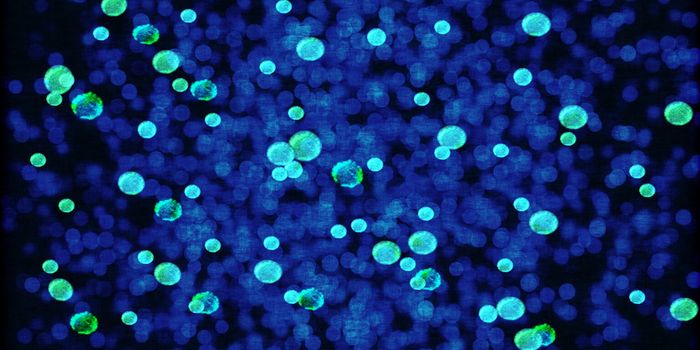

JAN 15, 2018CancerWith the help of a glow-producing natural enzyme, researchers detected the death of a single cancer cell quickly -- with ...